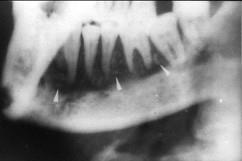

慢性中央性颌骨骨髓炎的治疗应 ( ) A.切开引流 B.及早拔除病灶牙 C.大剂量抗生素控制感染 D.全身支持疗法 E.死骨刮除、病灶牙拔除

问题 慢性中央性颌骨骨髓炎的治疗应 ( )

选项 A.切开引流 B.及早拔除病灶牙 C.大剂量抗生素控制感染 D.全身支持疗法 E.死骨刮除、病灶牙拔除

答案 E